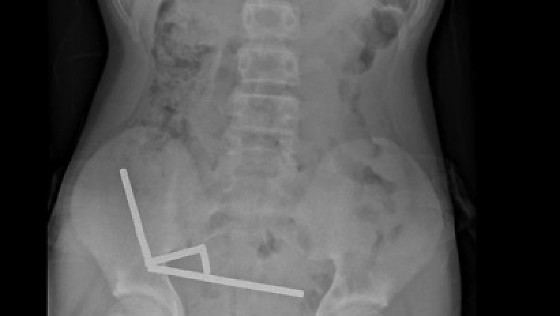

Exames revelaram que os ímãs haviam se agrupado em quatro correntes na parte inferior direita do abdômen, unindo diferentes seções do intestino com sua força magnética, segundo o relatório, que observou que algumas imagens foram distorcidas pelos ímãs. Os médicos então procederam com uma cirurgia exploratória.